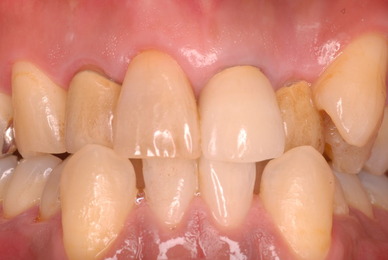

歯周病の疑いで東京のかなり遠方の方が来院されました。

驚くべきことですが、定期検診は受けていたそうです。しかしながら歯周病の指摘は受けたことがないそうです。

何故か?定期検診が虫歯のチェックのみになり、又肝心の歯周病の検査や歯周病の部分の予防や治療のためのブラシの使い方などを学んだ事がないのです。